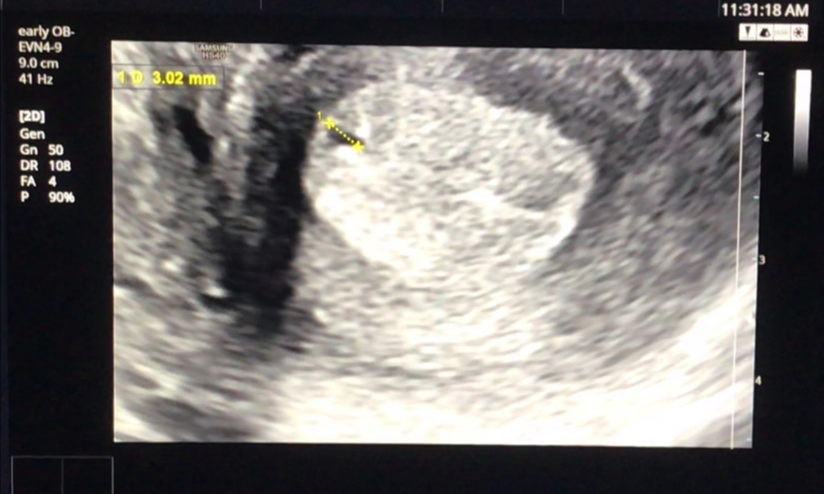

토요일에 원장님을 만나 뵙고, 원장님은 아기집이 보이고 임신은 맞는 것 같지만 아직 주변에 부모님을 포함하여 아무에게도 알리지 말라고 했습니다. 너무 초반이라 아이의 심장소리를 듣기 전에는 매우 조심하라고 강조하셨고, 우리는 누구보다 조심할 준비가 되어있었습니다.

그리고 다시 2주 뒤 산부인과를 찾았을 때 아기의 심장은 뛰고 있었습니다. ㅠㅠ